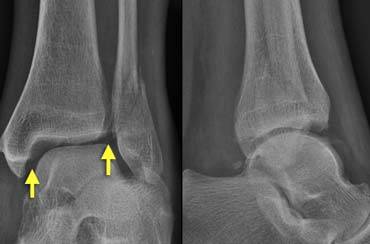

On the left image a Weber A or SA-fracture.

This ankle is stable because there is only an avulsion fracture of the lateral malleolus below the level of the syndesmosis.

The ring is broken in only one place.

On the right image there is an unstable fracture.

The ring of the ankle is broken in two places.

There is a lateral fracture and on the medial side there is a rupture of the collateral ligament allowing the talus to dislocate laterally.

Stability (4)

The medial clear space should not exceed 4 mm and is usually equal to the distance between the tibial plafond and the talus.

Widening of the medial joint space up to 6 mm or more requires disruption of the medial collateral ligament.